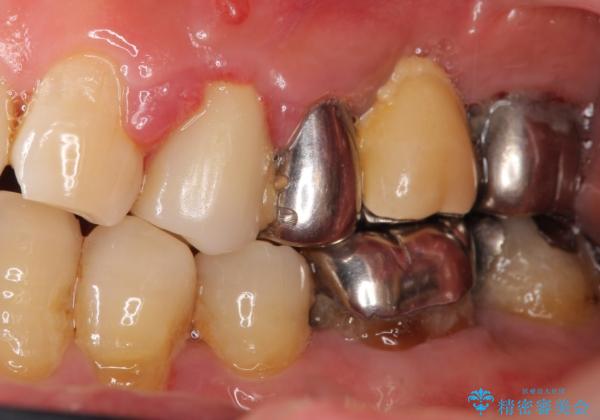

インプラント・ブリッジ・入れ歯の選択肢を提案させて頂いたところ、ブリッジをご希望されました。

保存不可能な歯(左上4)を抜去後、ブリッジによる補綴治療を行いました。

自然な仕上がりと咬み心地に喜んで下さいました。

歯茎の腫れも治り、ご満足頂けました。

クラウンの種類:メタルボンドクラウン エコノミー